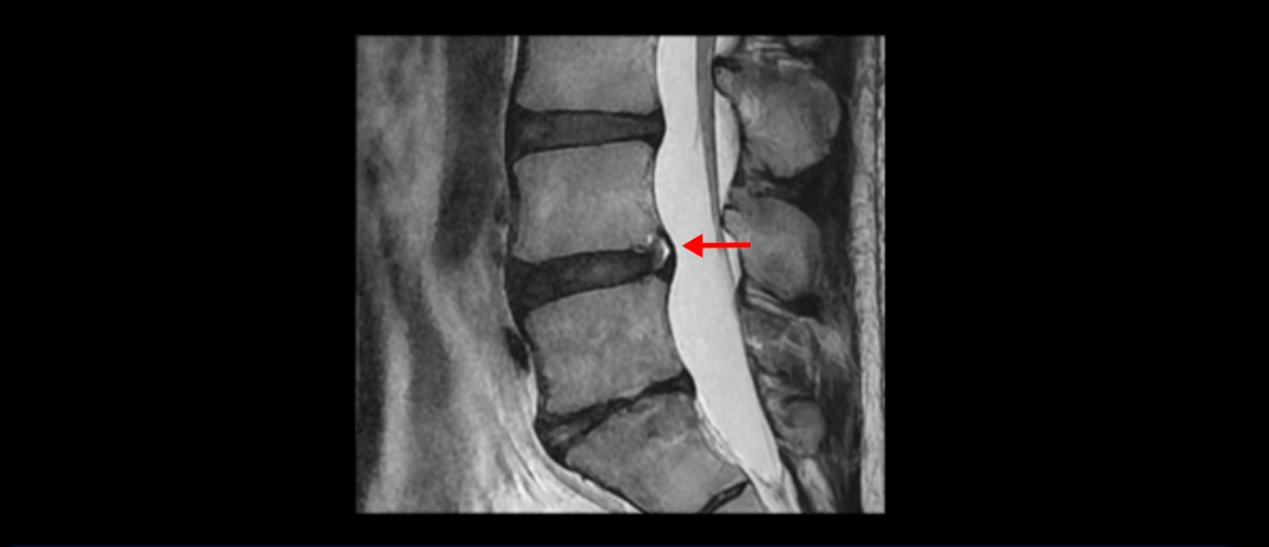

우선 이분 MRI를 보면 허리 모든 마디의 디스크가 퇴행되어 있고

여러 마디의 디스크가 조금씩 밀려나와 보이고, 디스크 섬유륜도 찢어져 보이는 마디도 보입니다.

그런데 이분의 증상과 MRI가 전혀 일치하지 않는데, 왜 그런지 지금부터 자세히 설명드립니다. 이분 증상은 앉으면 엉치와 허리가 심하게 아파 10분 이상 앉는 게 어렵고 양쪽 발가락이 앉아있을 때나 누워있을 때 다 저립니다. 걸을 때도 아파서 10분 걷기도 어렵습니다. MRI를 마디마디 살펴보면 1번 2번은 오른쪽으로 살짝 밀려나온 디스크가 있지만 전혀 심하지 않고, 뒤에 또 설명하겠지만 최근에 밀려나온 급성 디스크가 아니고 오래된 디스크로 판단됩니다.

4번 5번은 가운데로 섬유륜이 찢어져서 디스크가 살짝 밀려나와 있지만 역시나 최근에 찢어지고 밀려나온 걸로 판단되지 않고 오래 전에 찢어진 흔적으로 보입니다.

5번 1번 역시 가운데로 디스크 조금 밀려 나와있지만 신경 공간 넓이는 아주 넓어서 신경 눌림 있을 거라고 예상이 안됩니다.

앞서 1번 2번, 4번 5번, 5번 1번의 디스크가 찢어지고 조금 밀려 나온 게 최근에 찢어진 게 아니고 오래된 걸로 보인다고 말씀 드렸죠. 왜 그럴까요? 만약 급성으로 찢어진 것이라면 아주 심한 디스크성 통증이 있겠죠. 기침이나 재채기를 하면 심하게 아프고 허리를 조금만 구부리거나 비틀면 아주 날카로운 통증들이 생길 겁니다. 그런데 이분은 이런 증상이 전혀 아닙니다. 또 디스크의 밀려나온 정도도 전혀 심하지 않기 때문에 이분이 가지고 계신 양쪽 다리 저림, 특히 이분은 누워있을 때도 양쪽 발이 발가락까지 쑤신다고 하는데 이정도 디스크 때문에 그런 증상은 생길 수가 없는 겁니다. 이처럼 이분의 가벼운 디스크 탈출은 이미 오래 전에 진행되었고 섬유륜 자체는 이미 아문 상태인데도 디스크내장증을 진단받은 환자들 중에는 본인이 섬유륜 파열 환자라고 끝까지 믿는 분들이 많습니다. 다시 말하지만 디스크내장증이라는 진단을 받은 환자들을 보면 거의 전부 다 섬유륜 파열 증상이 아닙니다. 증상이 완전히 다릅니다. 진단이 애초에 잘못되면 어떤 치료를 받아도 좋아질 수 없습니다.

이분은 어떤 한 병원에서 디스크 내장증 얘기를 들으셨는데요. 여기 보시는 것처럼 4번 5번의 하얀 HIZ(High Intensity Zone)을 보고 디스크 내장증의 근거로 얘기하는 병원들이 있는데,

이 HIZ는 섬유륜이 찢어졌다가 이미 아문 뒤에도 얼마든지 보일 수 있는 흔적일 가능성이 있어서 재채기를 하면 아픈지, 허리를 구부릴 때 날카로운 통증이 생기는가 등의 증상으로 구별해야 하는데 MRI만 보고 HIZ가 보이면 그게 마치 통증의 원인인 것처럼 얘기하는 의사들이 있습니다. 이분 MRI를 자세히 보고 증상을 정말 자세히 들어본 의사가 있었더라면 다른 환자분들처럼 증상과 MRI가 일치하지 않는다는 얘기를 들을 수 있었을 텐데 이분은 그런 얘기는 듣지 못했습니다.